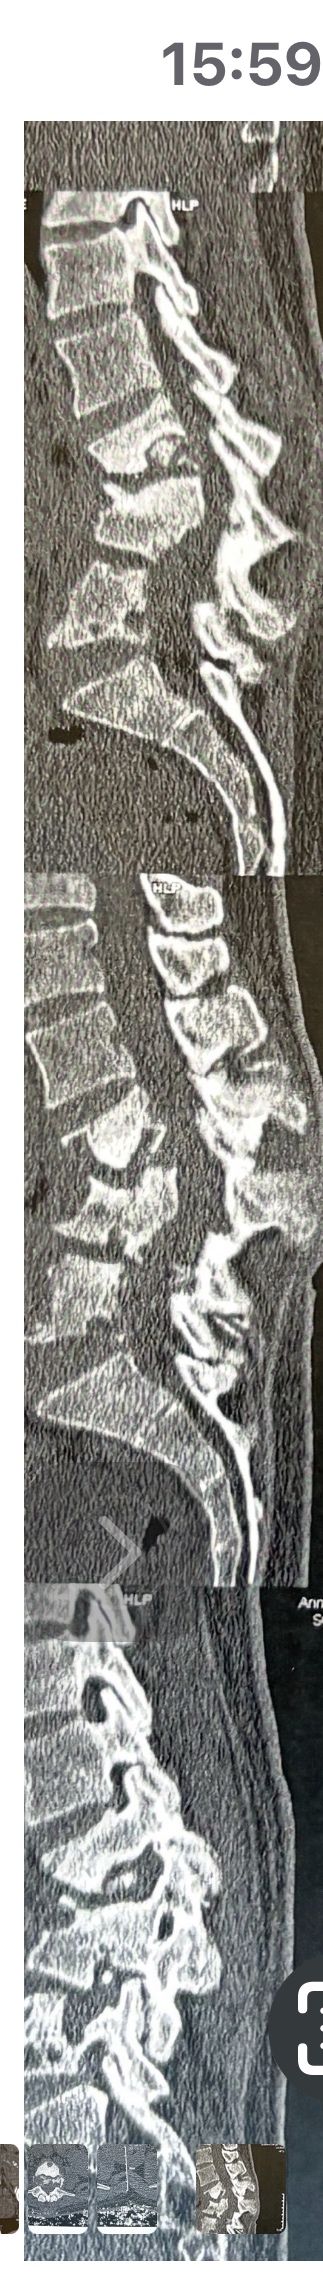

62 years old male presented to our clinic due to legs heaveness/tireddness in walking 2 weeks ago. 9 months ago had cervical disc herniation surgery. Had no LBP, no radicular pain. All neuro exam were normal. In his mri and dynamic scan there was a big osseous mass behind L5and S1. In his x. Ray report just was mantioned DJD

Radiologist missed that large osseous mass. Radiologist missed that bony post mass in x ray and mri. We ordered CT scan.